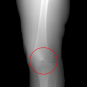

In this section, we provide qualitative and quantitative results of the two proposed diffusion-based methods and compare them with the baseline U-Net model. The first column of Fig. 3 showcases six randomly selected conditions: (a0)-(c0) show contour segmentations, and (d0)-(f0) denote segmentations containing contour and bones. In Fig. 3 (a1)-(f1), the images generated by U-Net contain blurred fine details in locations where bones overlap, despite maintaining the given shape, as highlighted by the red circle. In contrast, the results from CSM appear more realistic than the U-Net. However, their quality decreases with introduced constraints, as indicated by the red arrow in Fig. 3 (d2) and (f2). The results from CTM not only achieve nearly the same level of fineness as the labels but also provide reasonable results with respect to the given conditions as illustrated in the fourth column.

Table I summarizes the quantitative results averaged across all testing data. The evaluation metrics include mean absolute error (MAE) and peak signal-to-noise ratio (PSNR). We observed that CTM performs substantially better than U-Net and CSM under both segmentation-based conditions, and CSM performs worse than the U-Net.

Unlike the U-Net which learns a mapping function between input and output, the diffusion models can implicitly capture the underlying data distribution from the training data and then sample it, preventing the loss of fine details on the pixel level. However, in CSM, conditions are incorporated only at the first sampling step while being perturbed, which results in imprecise conditional information. Instead, CTM provides an estimated score function of the conditional distribution for each sampling step, accommodating both reliability and realism. Nonetheless, presently generated X-ray images only encompass independent 2D conditional information, which may introduce geometric inconsistencies between a set of projections. Future research will focus on modeling 3D probabilistic distributions with the provided 2D conditions to enable CT reconstruction from the generated projections. In addition, clinical datasets will also be incorporated.